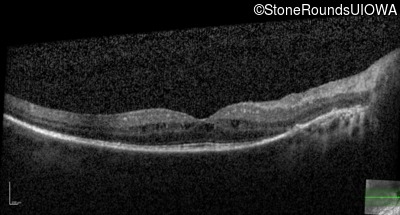

OCT Stack

20/32